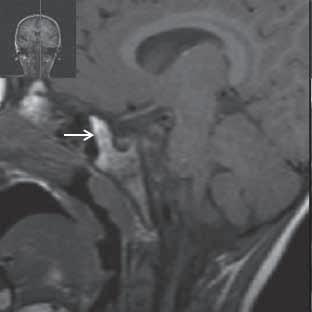

Obr. I.1.7a Sestup mozečkových tonzil (šipka), Chiariho malformace I

Obr. I.1.7b Sestup mozečkových tonzil, „pek like“ (šipka), Chiariho malformace I c d

Sestup mozečkových tonzil,

Myelomeningokéla